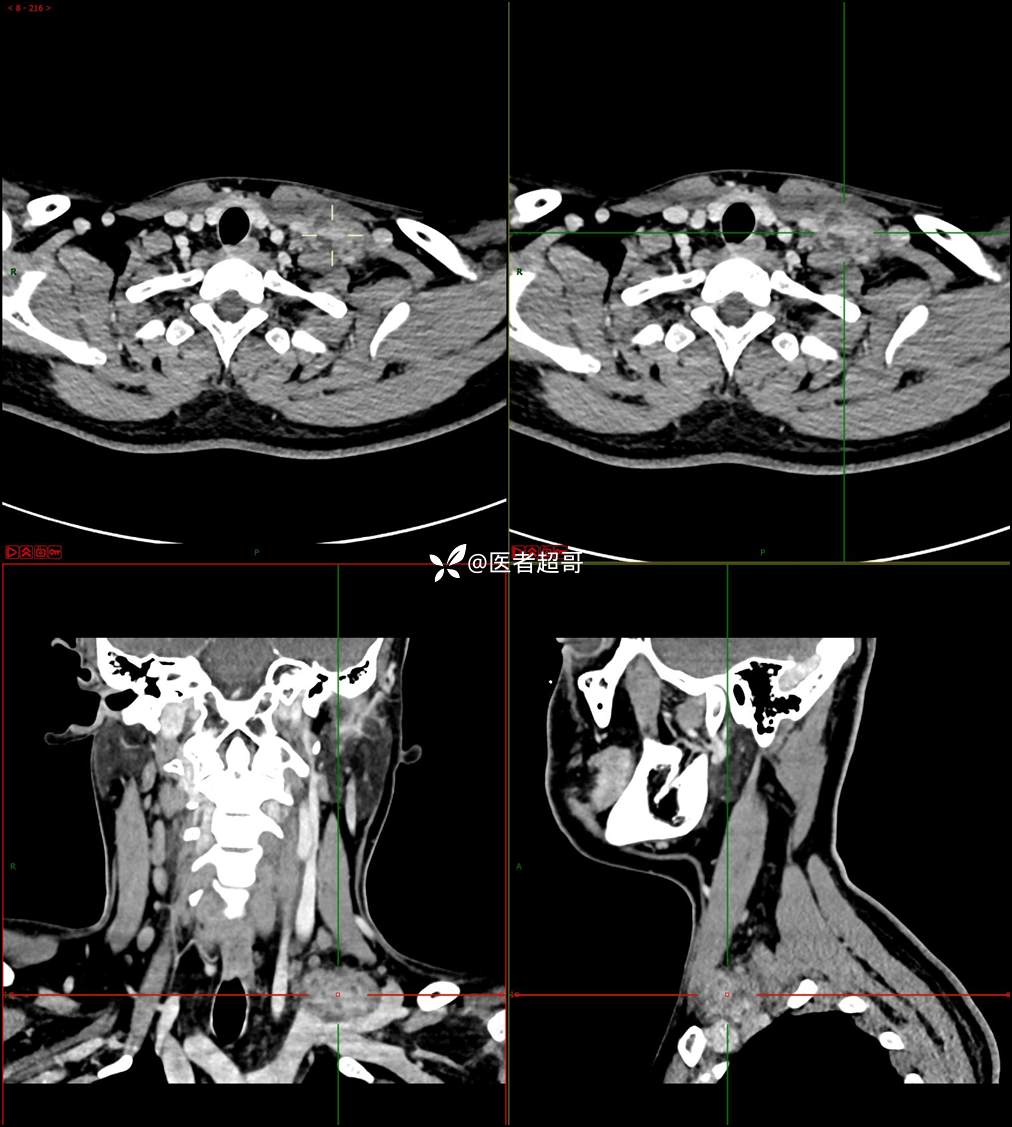

现病史:患者自述10余天前无意中发现左侧颈部一肿物,颈部活动时、进食时伴疼痛,无发热,患者前往人民医院就诊,给予输液治疗(头孢呋辛钠2g bid 硫酸阿米卡星0.4g qd、)10天,患者感肿物轻微变小,后患者为求进一步治疗,昨日来我院门诊就诊,给予颈部彩超示:左颈部实性肿物,神经来源?,左颈部肿大淋巴结;颈部ct平扫+强化示:左侧锁骨上区占位,神经鞘瘤?双侧颈部多发淋巴结;门诊以“局部肿物”收治入院,患者自患病以来,神志清,精神可,饮食睡眠可,体重无明显变化,二便正常。